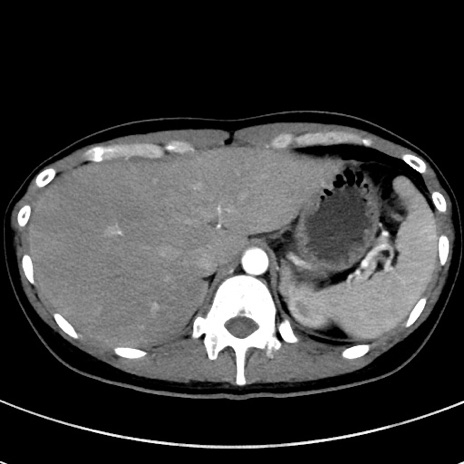

症例17(横断像)

【症例】20歳代女性

【主訴】嘔吐、下腹部痛

【現病歴】昨日夕食後に嘔吐し下腹部痛が出現。本日になっても嘔吐持続し改善しないため来院。

【身体所見】意識清明、BT 37.2℃、BP 108/67mmHg、腹部:平坦、やや硬、下腹部正中から右にかけて圧痛あり、反跳痛軽度あり、tapping pain(+)。

【データ】WBC 13600、CRP 14.94